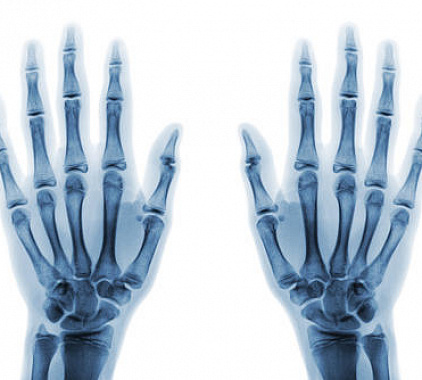

Рентген правой руки и левой руки проводится комплексно, с целью визуализации костной структуры пястья, запястья и фаланг пальцев. Получаемые в нашей многопрофильной клинике трехмерные снимки на аппарате с технологией MultiTom Rax позволяют с точностью идентифицировать травматические и деформационные изменения (переломы, трещины, вывихи, подвывихи, растяжения, разрывы), артриты и артрозы, новообразования и опухоли, а также аномальные изменения в процессе развития.

- Структура костей однородная, контуры визуализируются четко (непрерывно), нет повреждений травматического характера, изменения соотношения суставных поверхностей;

- Суставные щели регистрируются в корректной размерности, нет признаков увеличения или сужения, наблюдается наличие оси симметрии;

- Анатомическое положение и форма мелких костей пястья и запястья (а также лучезапястного отдела) в норме, нет аномалий или опухолей.